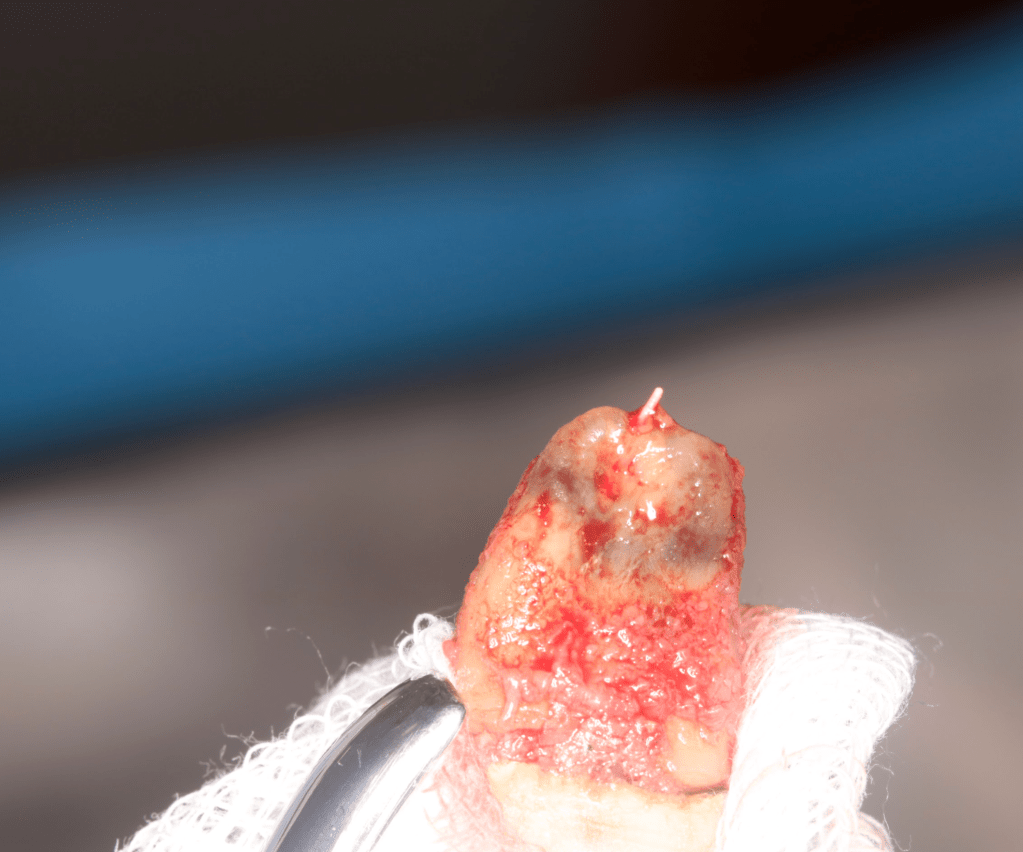

Autotansplantes

REIMPLANTES

Intencional por dificil acceso coronal y quirúrgico

Reinplante por fracaso de tratamiento

Reimplante, istmo apical, curación cortical palatina 1 año